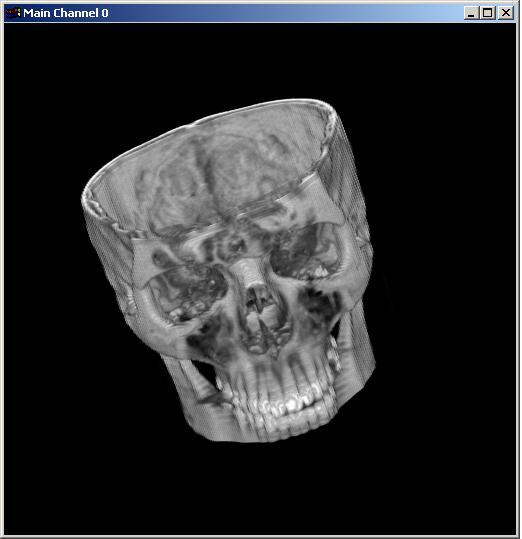

Visible human male CT data

Data

Resolution : 256x256x128

|

Visible human male CT data

Data

Resolution : 256x256x128

|

The following 12

images was generated by PC which has NVIDIA's GeForce3 GPU graphics card. The

hardware accelerated rendering techniques are used to make the following images.

To use the GeForce3 hardware, we have to use the OpenGL extensions like

GL_NV_texture_shader2, GL_NV_register_combiners, GL_EXT_texture3D,

GL_EXT_paletted_texture, GL_ARB_multitexture and so on. Since the GeForce3 card

allows the 3D texture shading, the image quality is better than the pixel of

frame buffer based shading in showing two materials at the same time.